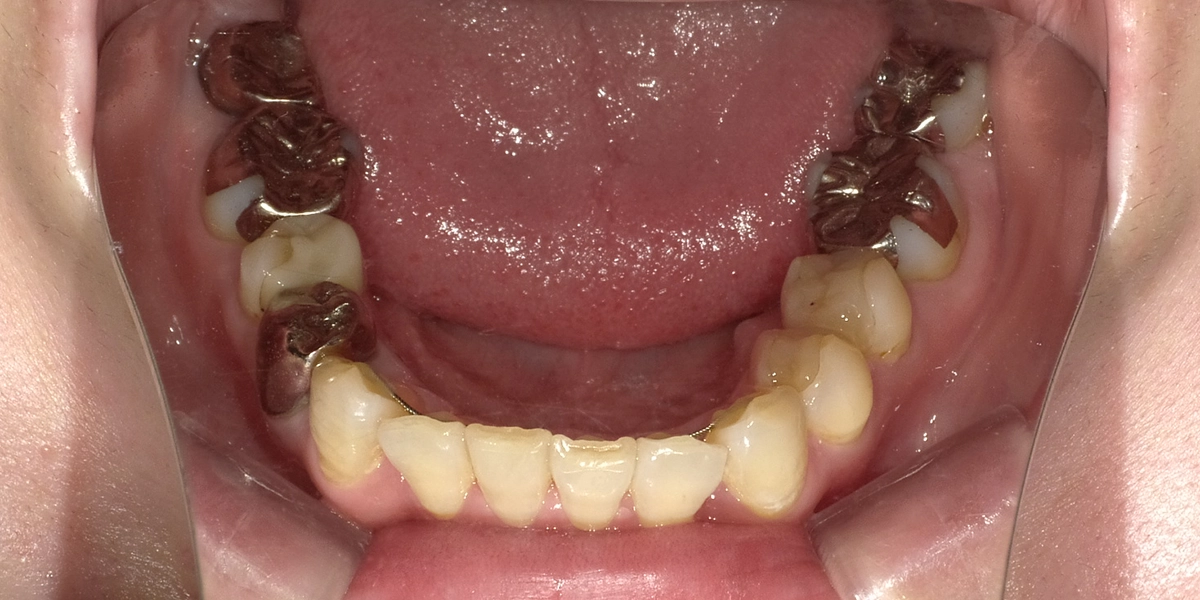

治療前の下の歯

下の歯並び

下の前歯がガタガタして、歯並びが整っていないのが分かります。これが患者様の一番のお悩みでした。